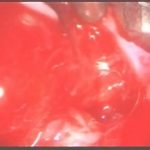

術中写真

摘出 中